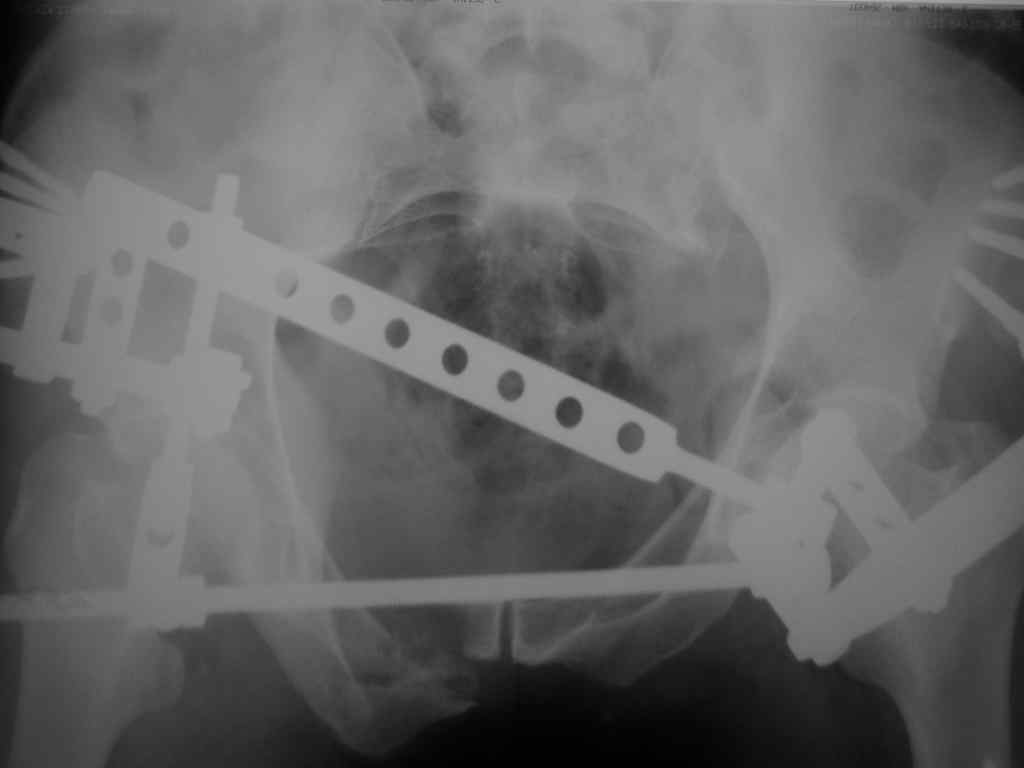

Снимки вот